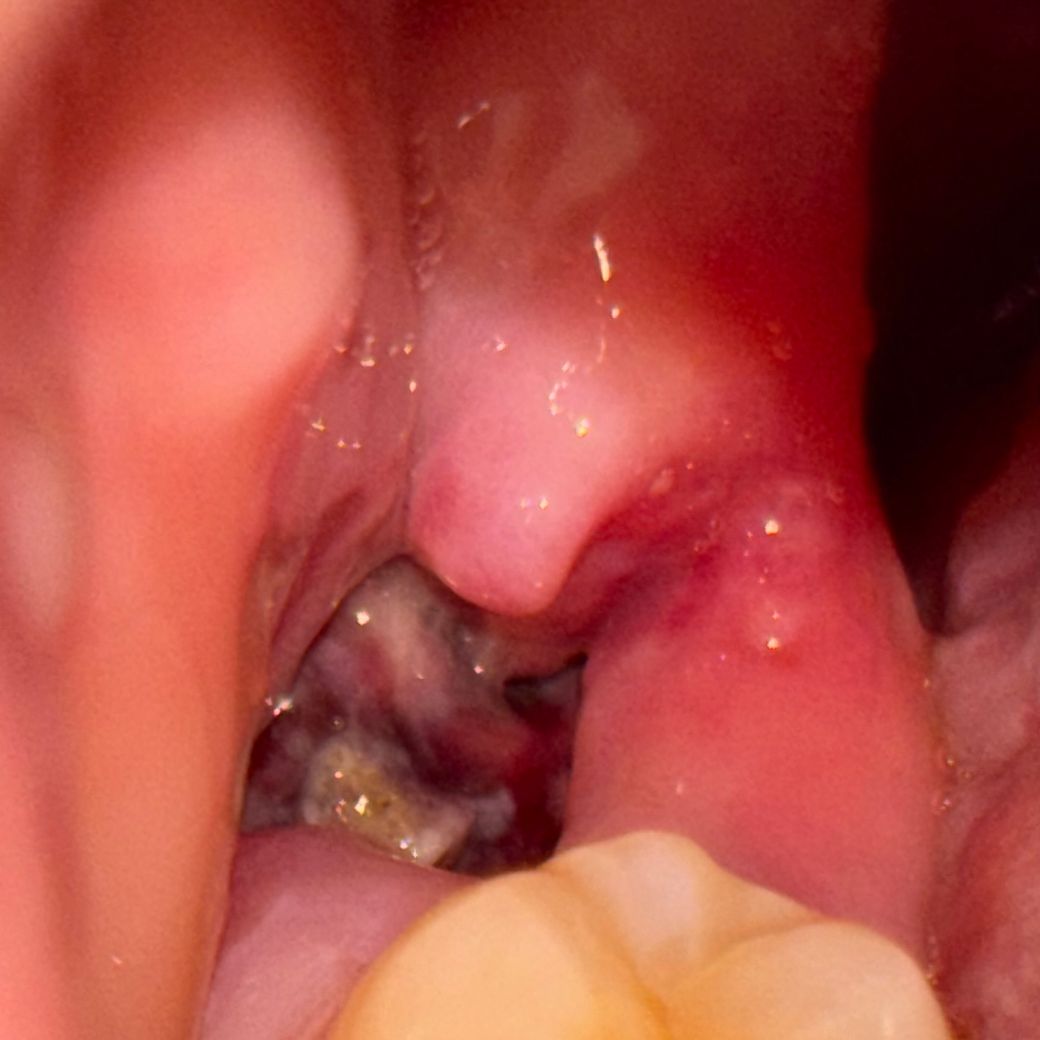

사랑니 발치한지 1주일되는날인데 드라이소캣일까요?ㅠㅠㅠㅜㅠ

혈병은 잘 있는듯한데 사진처럼 흰막같은게 조금 군데군데 있고, 입을 크게 벌려먹을때 아프더라고요ㅠ 가만히 있을땐 안 아프더라구요? 근데 보통 일주일 지나면 안 아프지않나요? 전에 뽑았을땐 잇몸차오를때까지 쭉 통증이 없었는데 이번에 뽑은건 왜 이럴까요? 치과왈 저번껏보다 뼈를 더깎았다고했나? 그래서 저번보다 더 아플꺼라고했었긴했는데 드라이소캣? 그런거면어쩌죠? 병원을 가봐야할까요?ㅠㅠ

드라이 소켓은 감염의 일종으로 통증이나 냄새가 심하게 납니다. 통증이 없다면 크게 걱정은 안하셔도 될것같습니다.

2. 드라이소켓 양상은 아닐것 같습니다 걱정마세요